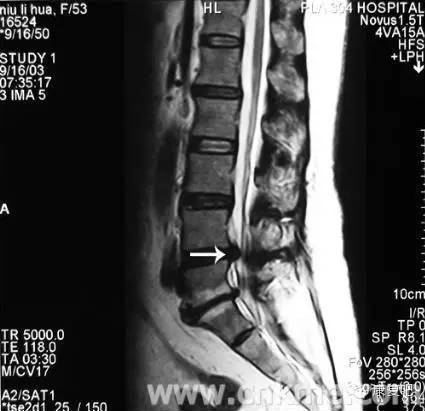

3、核磁共振攝影(MRI)

可顯示出狹窄的部位(脊髓腔的狹窄)、椎間盤物質(zhì)的突出進(jìn)入脊髓腔、或受侵害之脊髓神經(jīng)根。